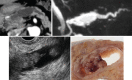

Endoscopic ultrasound (EUS) is a key modality for the evaluation of suspected pancreatic cystic neoplasms (PCNs), as the entire pancreatic gland can be demonstrated with high spatial resolution from the stomach and duodenum. Detailed information can be acquired about the internal contents of the cyst(s) [septum, capsule, mural nodules (MNs)], its relation with the main pancreatic duct (MPD), and any parenchymal changes in the underlying gland. PCNs comprise true cysts and pseudocysts. True cysts can be neoplastic or nonneoplastic. Here, we describe serous cystic neoplasm (SCN), mucinous cystic neoplasm (MCN), and intraductal papillary mucinous neoplasm (IPMN) as prototype neoplastic cysts, along with nonneoplastic lymphoepithelial cysts (LECs).